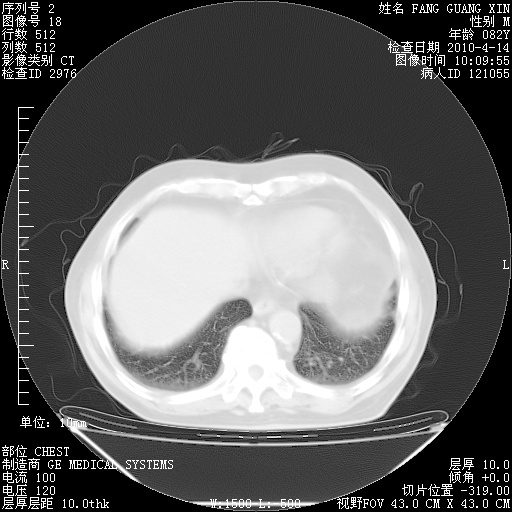

楼主| 发表于 2010-4-28 16:59 | 显示全部楼层

4月28日肺部CT——再次出现类似去年5月9日——透光度降低,(影像科认为)“间质性”改变。

楼主| 发表于 2010-4-28 17:00 | 显示全部楼层

4月28日肺部CT——再次出现类似去年5月9日——透光度降低,“间质性”改变。

楼主| 发表于 2010-4-28 17:02 | 显示全部楼层